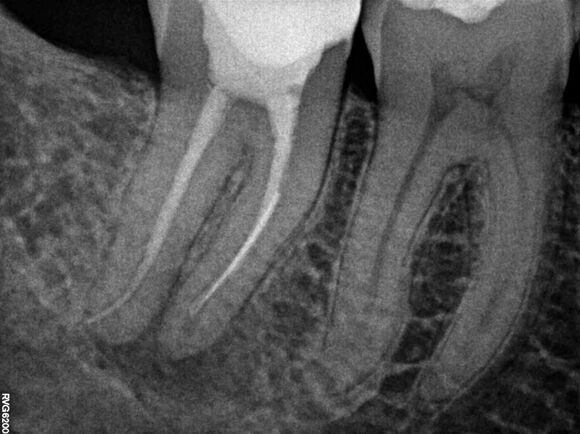

Beispiel 2: Vorher

Ausgedehnte Entzündung neben einem Implantat, bei diesem Überweisungsfall.

Beispiel 2: Nachher

Nur 6 Monate später ist die Entzündung fast vollständig zurückgegangen - Zahn und Implantat sind gerettet.